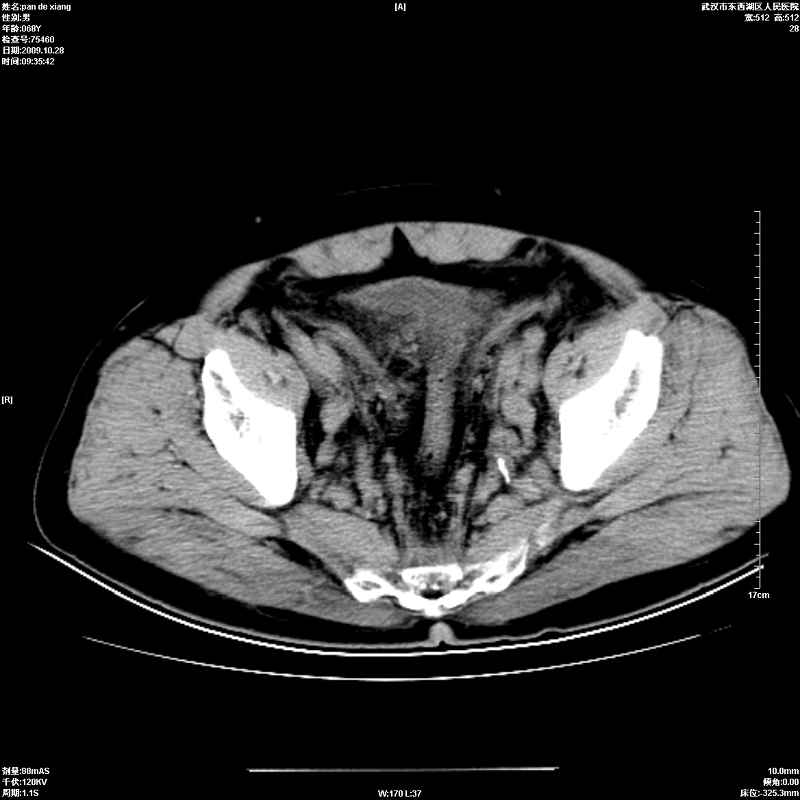

以下是引用杀毒软件在2009-10-28 20:41:00的发言:[br]结合临床考虑---白血病双肾改变或淋巴瘤。

以下是引用zxl51642在2009-10-29 9:59:00的发言:[br]结合临床“单克隆免疫球蛋白血症”,考虑双肾为继发损害并肾功能不全(尿中大量igg及少量iga、igm等大分子免疫球蛋白滤出所致继发损害),椎前软组织肿块为髓外造血。与浆细胞瘤有区别,平扫时有战友说的很清楚。